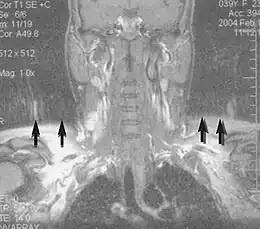

Magnetic resonance angiography (MRA) generates pictures of the arteries to evaluate them for stenosis (abnormal narrowing) or aneurysms (vessel wall dilatations, at risk of rupture). MRA is often used to evaluate the arteries of the neck and brain, the thoracic and abdominal aorta, the renal arteries, and the legs (called a "run-off"). A variety of techniques can be used to generate the pictures, such as administration of a paramagnetic contrast agent (gadolinium) or using a technique known as "flow-related enhancement" (e.g., 2D and 3D time-of-flight sequences), where most of the signal on an image is due to blood that recently moved into that plane (see also FLASH MRI).[53]